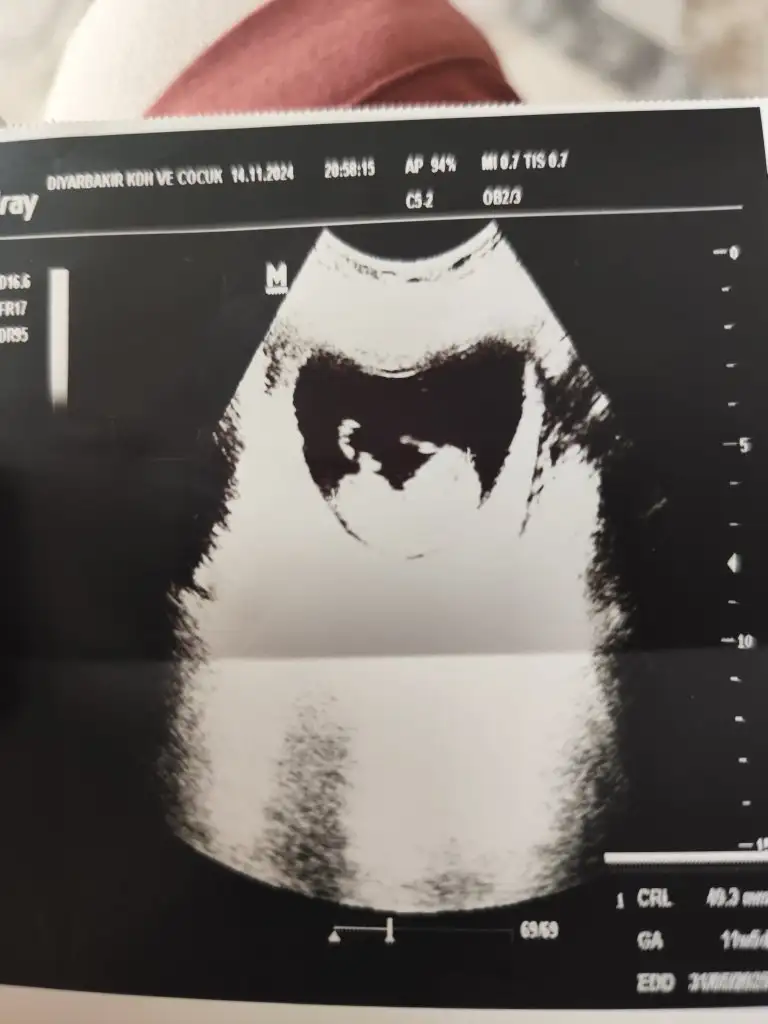

Merhaba benim bebeğimi de tahmin edermisiniz

Sata göre 11 haftalık